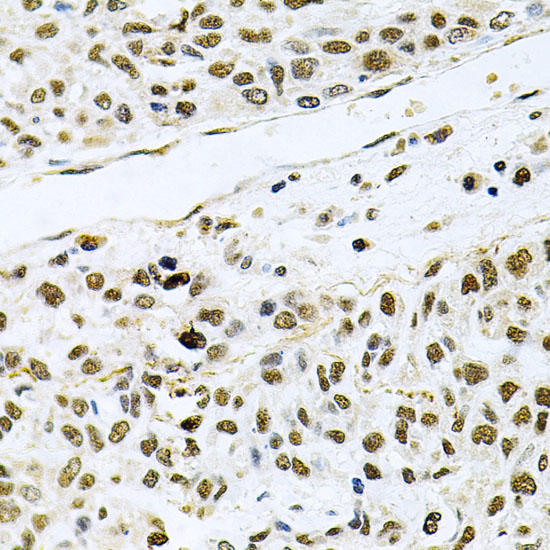

Immunohistochemistry of paraffin-embedded human lung cancer using MCL1 antibody at dilution of 1:100 (40x lens).

Immunohistochemistry of paraffin-embedded human gastric cancer using MCL1 antibody at dilution of 1:100 (40x lens).